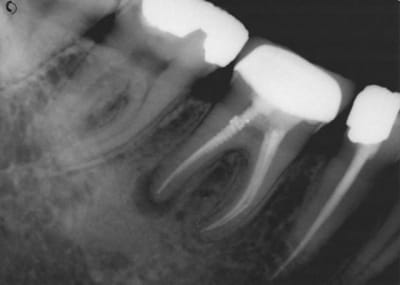

J'avais couronné... mais démontable, pas d'IC...

3 ans après (oui, on devait surveiller tous les 3 mois ;-)

(radio 3 mois après)

Voilà la fin.

Les deux dernières sont de 2011 et 2015.